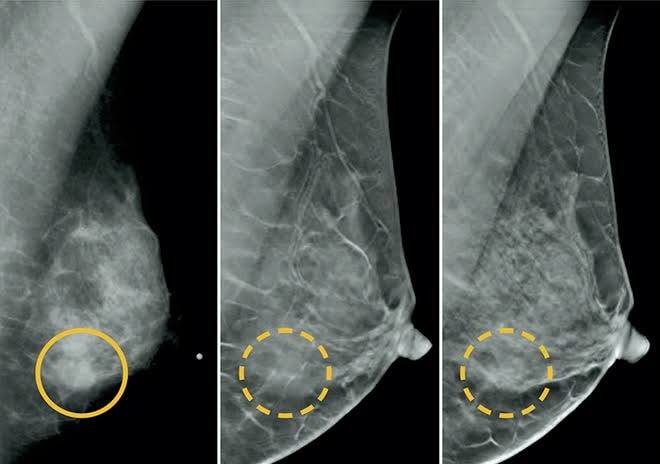

imagem sem descrição.